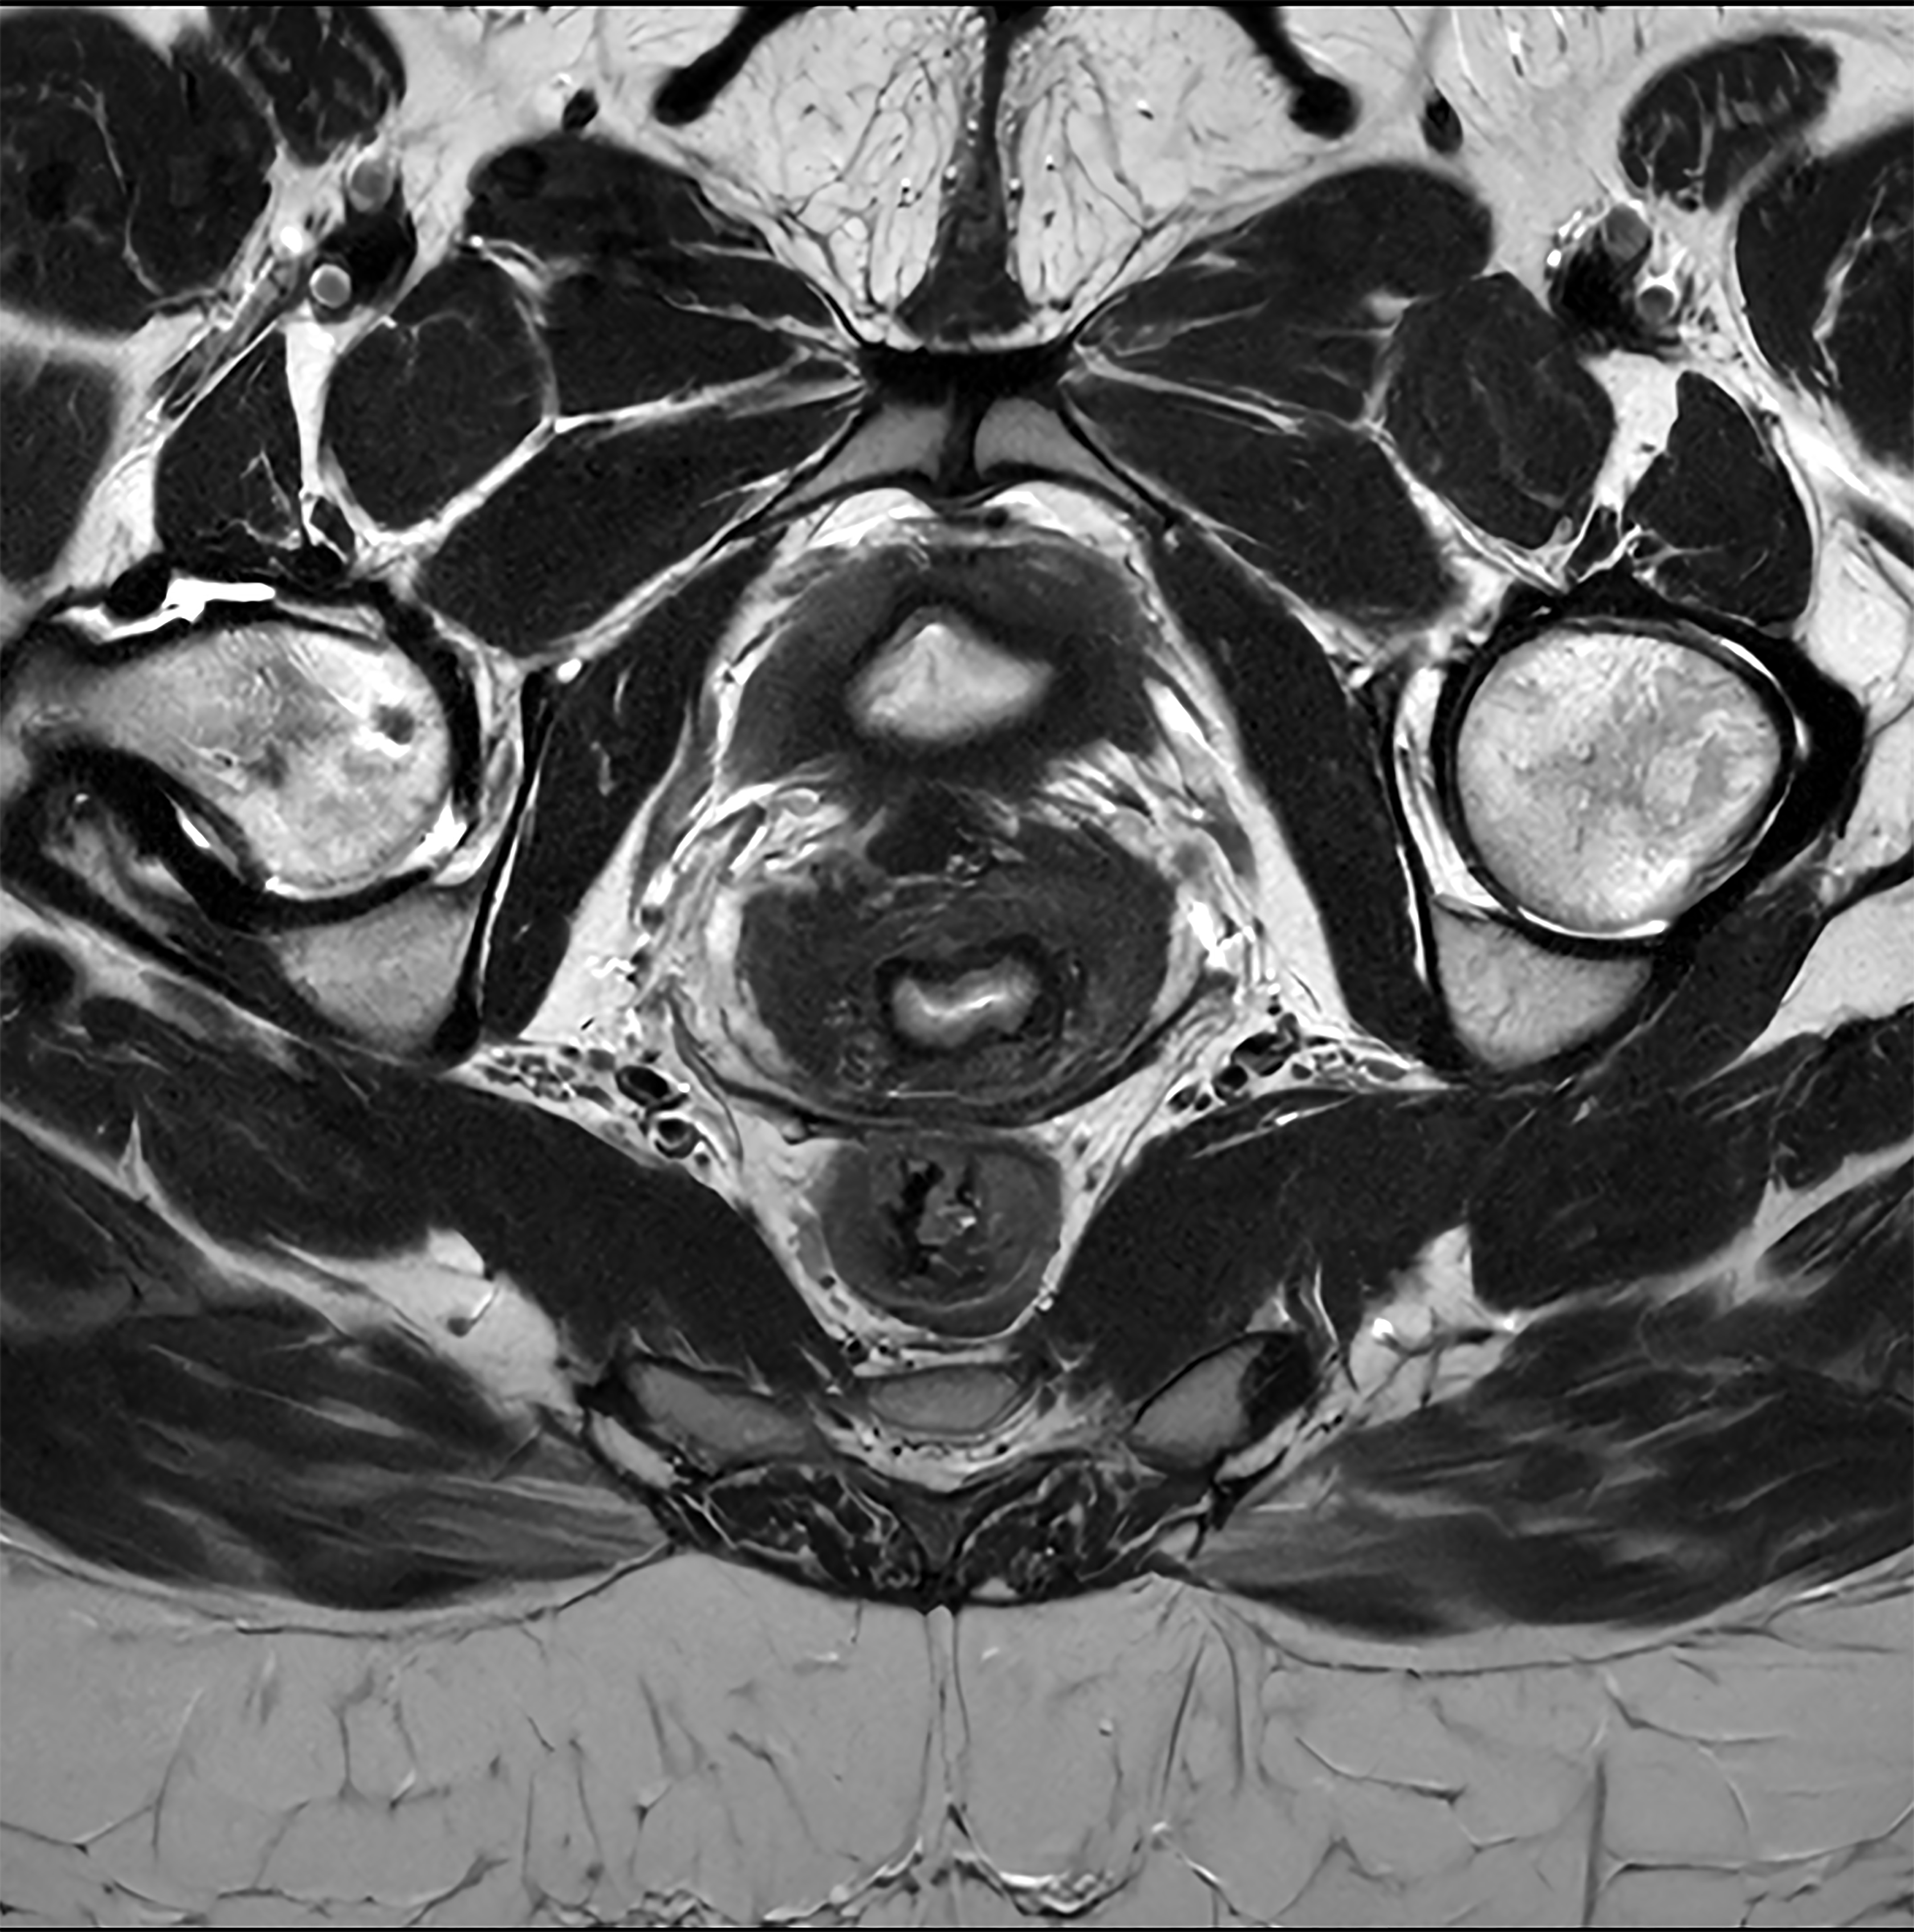

De nieuwste SmartSpeed Precise [1]-technologie verhoogt de productiviteit nog verder, waardoor scans tot drie keer sneller kunnen worden uitgevoerd [7] en de scantijd aanzienlijk wordt verkort terwijl de uitzonderlijke beeldkwaliteit behouden blijft. De kern van SmartSpeed Precise is de dual AI-engine, die zorgt voor een verbetering van 80% in de scherpte van de beelden [8], waardoor de visualisatie wordt verbeterd voor betrouwbaardere en nauwkeurigere diagnoses. Deze krachtige combinatie van snelheid en precisie zorgt ervoor dat radiologen subtiele afwijkingen duidelijker kunnen detecteren, wat uiteindelijk leidt tot betere patiëntresultaten. De nieuwe release van Philips – MR Workspace R12 [6] – introduceert een ‘zero-click’-workflow [9], die het gehele beeldvormingsproces naadloos begeleidt, van het starten van de scan tot het genereren van rapporten. Door handmatige handelingen te verminderen en de efficiëntie te optimaliseren, stelt MR Workspace R12 [6] radiologieafdelingen in staat de patiëntdoorstroming te verbeteren en achterstanden terug te dringen, waarmee tegemoet wordt gekomen aan de toenemende vraag naar snellere en nauwkeurigere beeldvorming. Een belangrijke innovatie binnen MR Workspace R12 [6] is de door AI aangestuurde SmartExam-functie, die 80% van de MR-procedures automatiseert [10], door werkzaamheden te stroomlijnen en beeldvormingsworkflows te standaardiseren.

Andere baanbrekende innovaties zijn onder andere Smart Reading [4], de eerste oplossing in de industrie die cloudgebaseerde, door AI aangestuurde kwantitatieve rapportage naadloos [11] integreert. Smart Reading maakt gebruik van geavanceerde AI-platformen zoals icobrain (icometrix) voor neurologie – inclusief detectie van de ziekte van Alzheimer – en QP-Prostate (Quibim) voor geavanceerde diagnose van prostaatkanker. Door objectieve, zeer betrouwbare diagnoses te leveren, maken deze zero-click AI-oplossingen [9] gestroomlijnde, op data gebaseerde besluitvorming mogelijk voor artsen. Met MR Workspace R12 [6], SmartSpeed Precise [1] en Smart Reading [4] blijft Philips de grenzen van AI in MRI verleggen om de efficiëntie, nauwkeurigheid en toegankelijkheid van diagnostische beeldvorming te vergroten en tegelijkertijd de weg vrij te maken voor de toekomst van autonome MR-scanning.